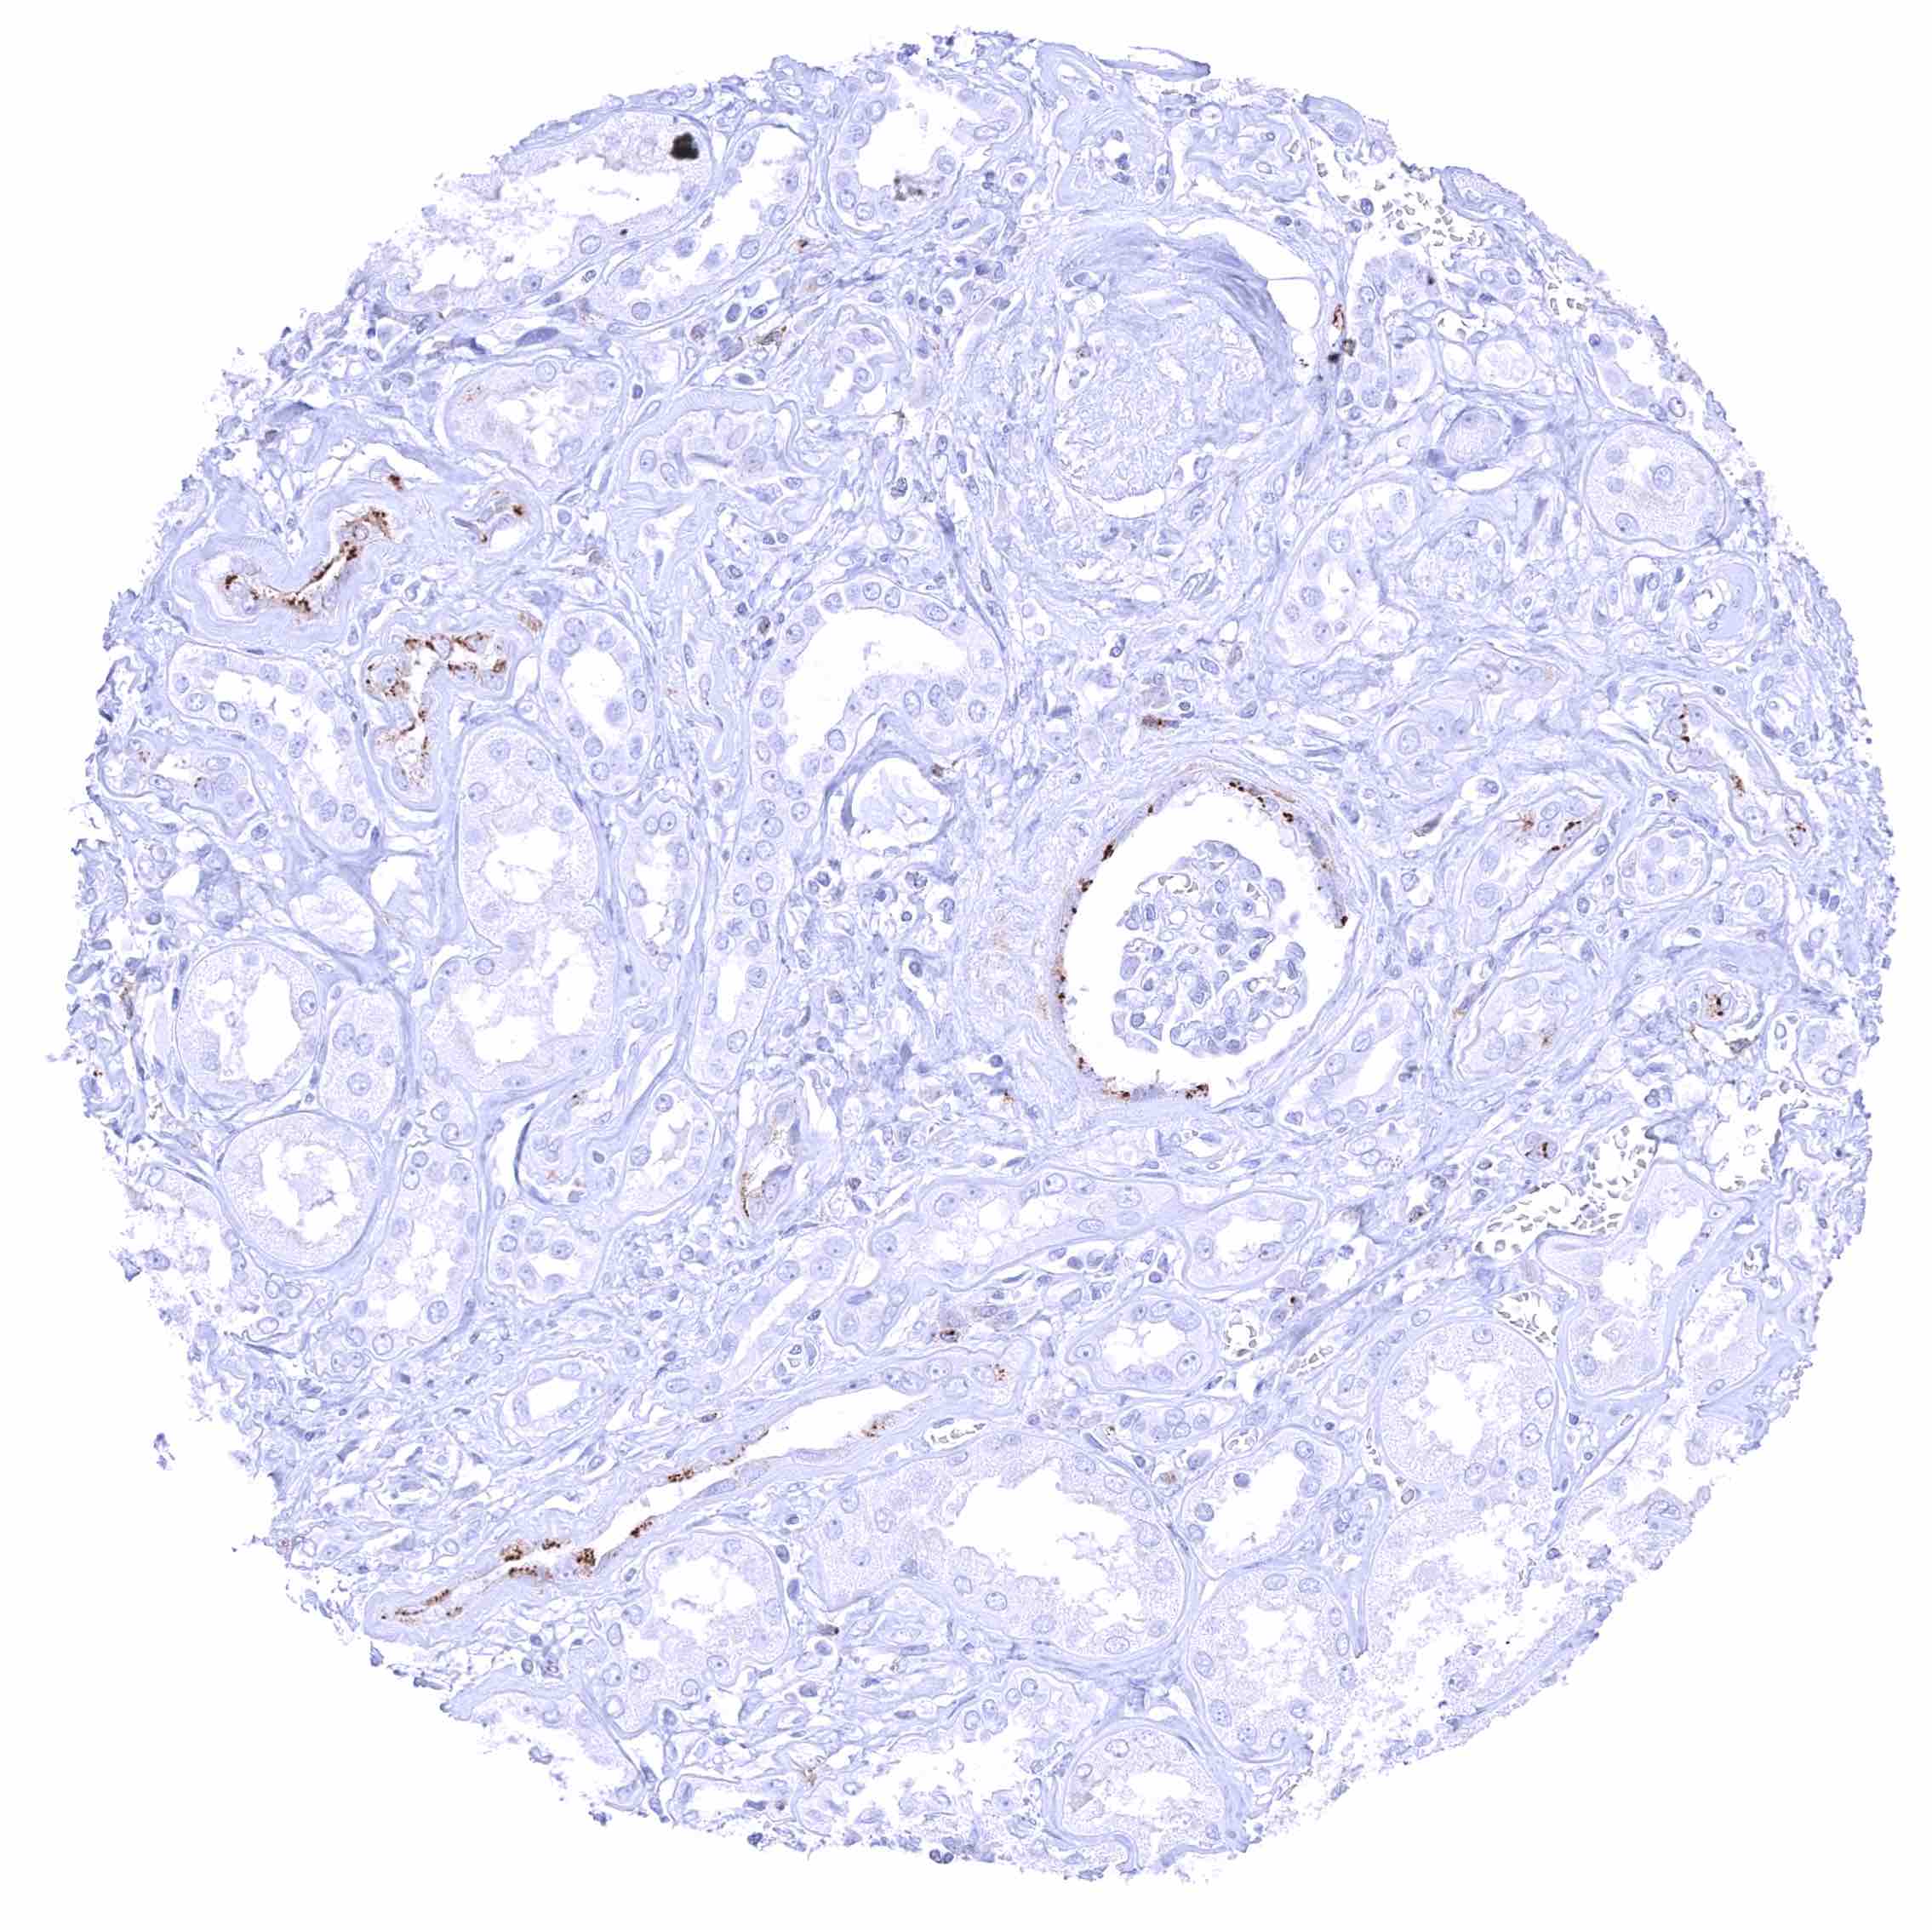

| Lymph node | Membranous CD70 staining of variable intensity in subsets of inflammatory cells (mostly lymphocytes). Most CD70 positive cells are interfollicular. | |

| Spleen | Membranous CD70 staining of variable intensity in a fraction of cells. | |

| Tonsil | Membranous CD70 staining of variable intensity in subsets of inflammatory cells (mostly lymphocytes). Most CD70 positive cells are interfollicular. Squamous epithelium remains CD70 negative. | |

CD70 expression is most commonly seen in different types of lymphoma and in clear cell renal cell carcinoma. Other cancer types have also been described to express CD70 at lower frequency.